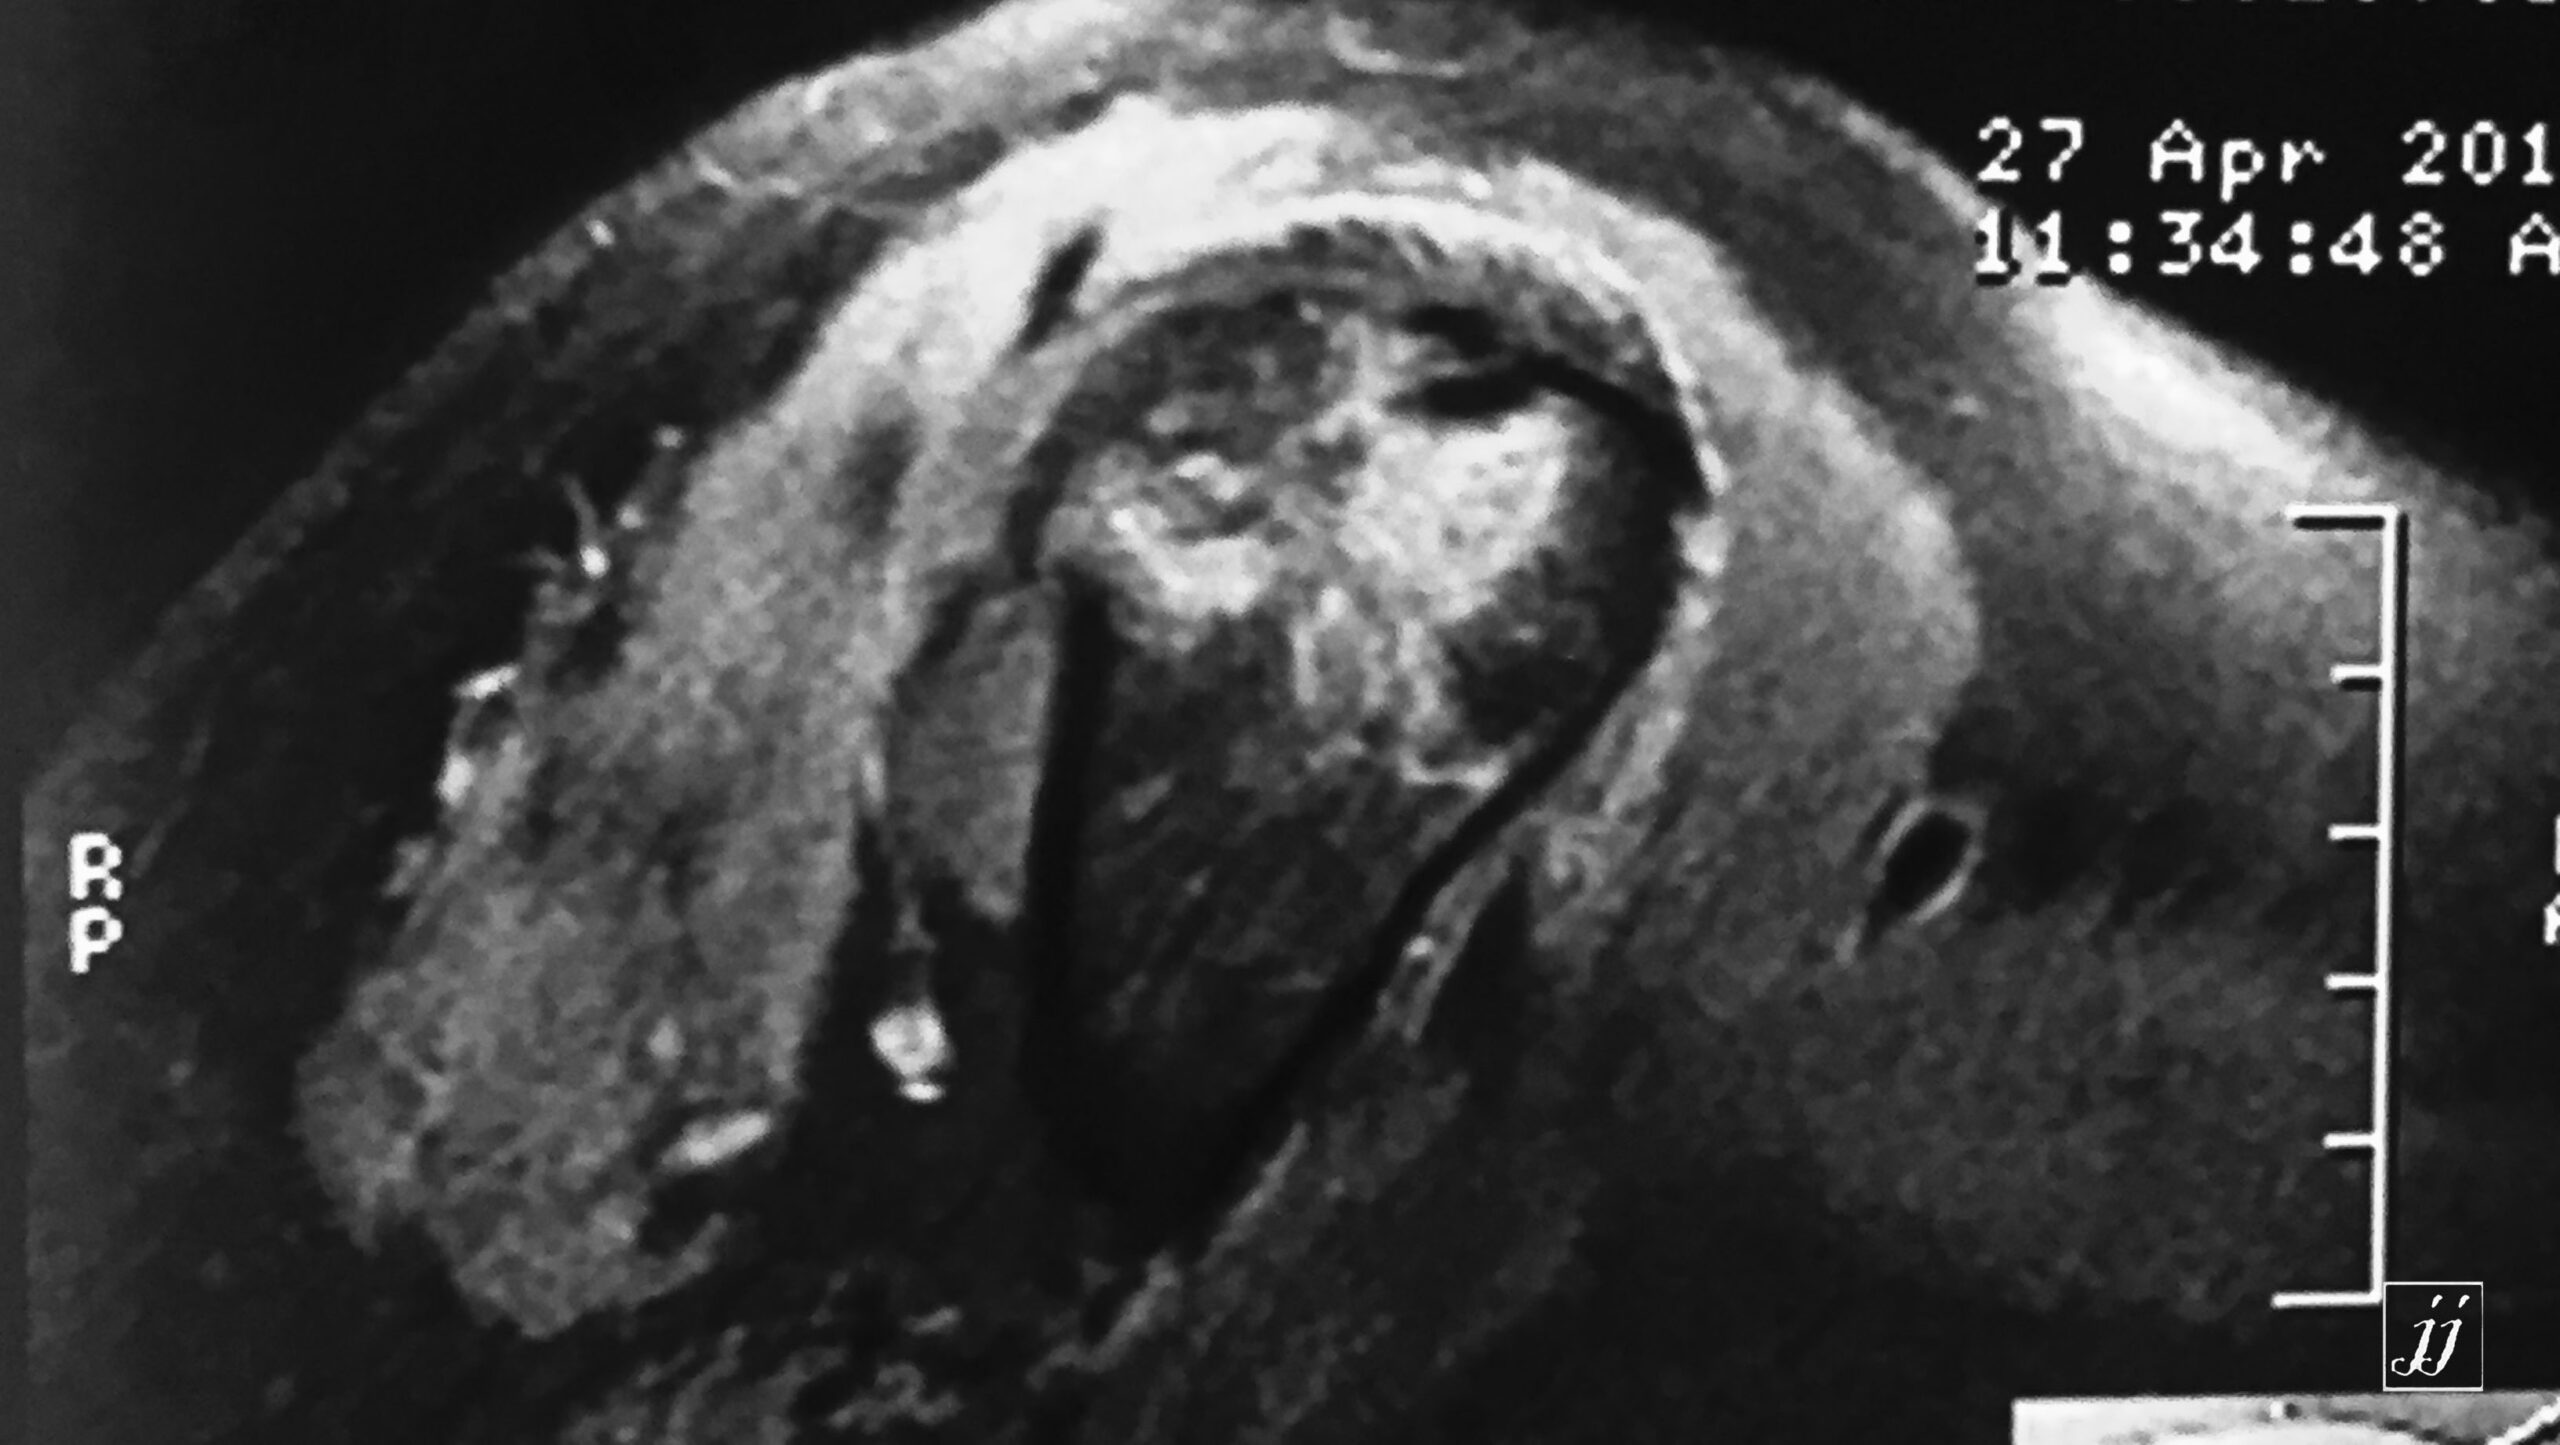

MSK- detached bone fracture of grater tuberosity and bone bruising (5)